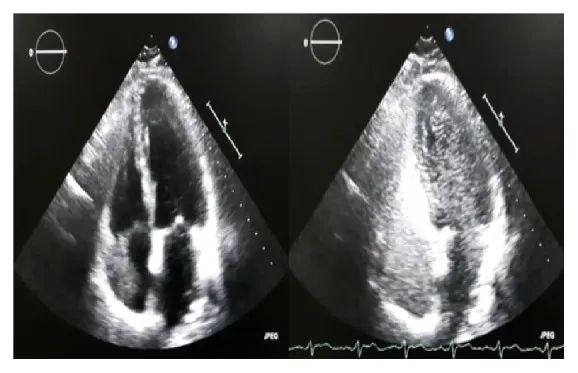

进行经胸超声造影。在右心房出现后的5个心动周期内,对比剂的微泡出现在左心房和左心室(图3和4)。

图4 经胸超声心动图显示心脏左侧有微泡造影剂